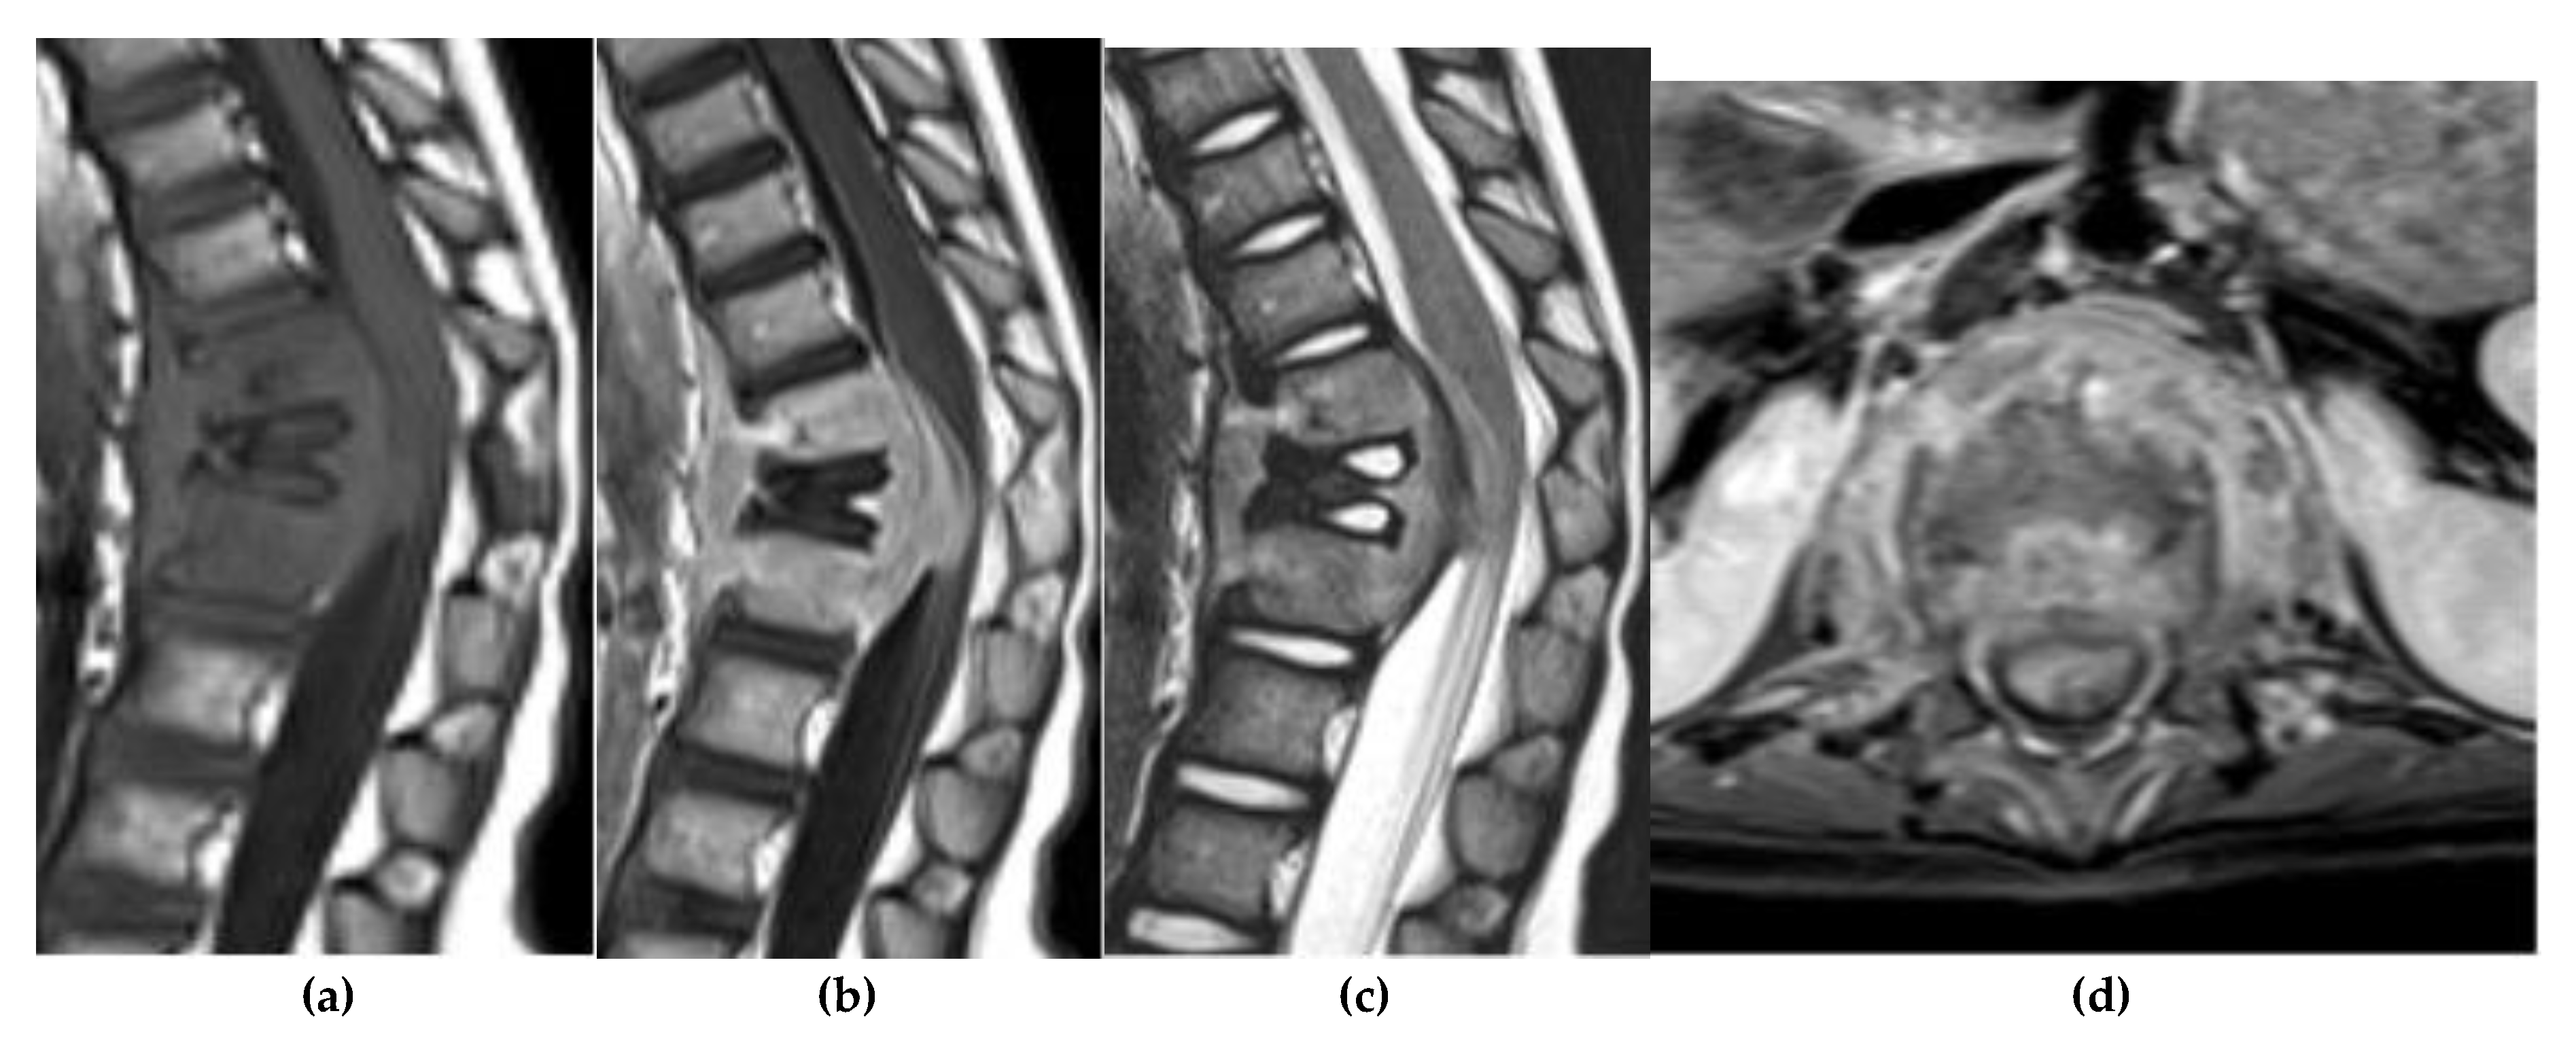

Giant Cell Tumor